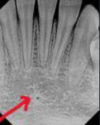

identify the anatomical structure below.

mandibular canal